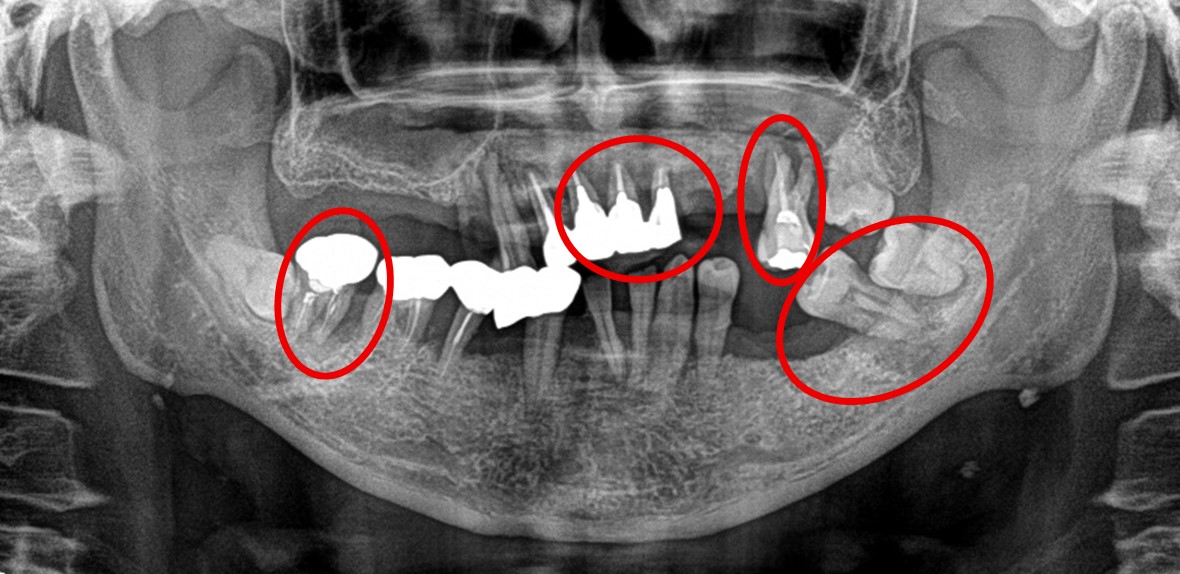

男性Iさん 50代 (マグネット式入れ歯)

治療内容

歯周病が進行し深刻な状態でした。保存することができない歯が上4本、下3本ありましたので、抜歯し、残った歯上4本、下7本の歯周病治療を徹底的にし、それらの歯を活用し上下マグネット式総入れ歯を入れました。

Before

赤丸は抜歯しました。上4本、下3本